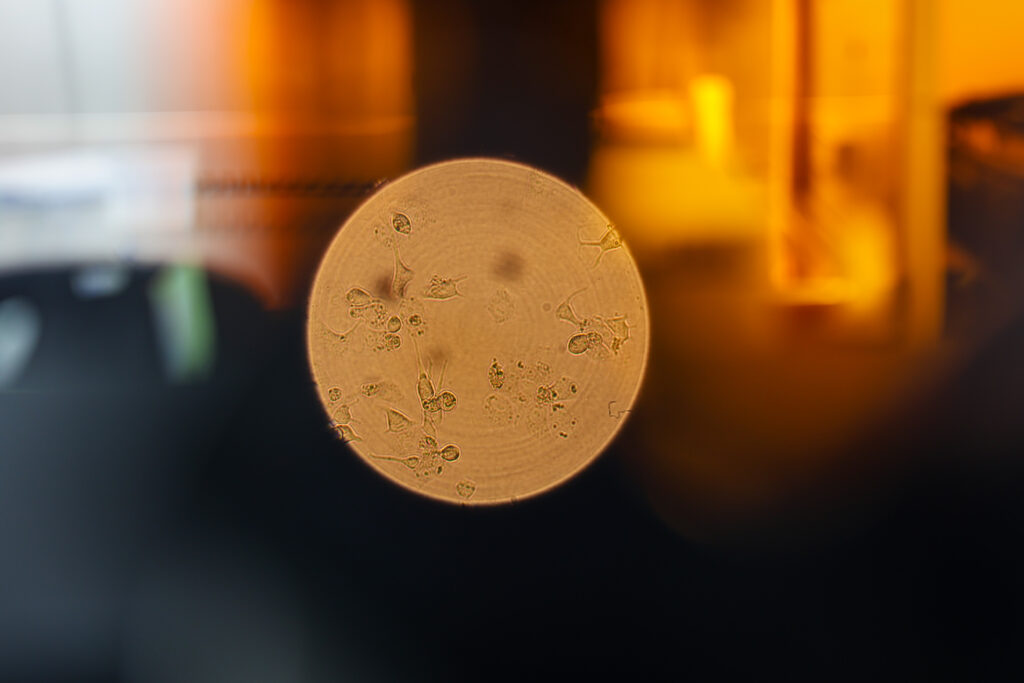

Desde el Instituto Venezolano de Investigaciones Científicas (IVIC), en el Centro de Microbiología y Virología Celular, se desarrollan diferentes proyectos de investigación para poder entender el comportamiento viral y brindar herramientas de cómo enfrentarlos.

«La virología como ciencia estudia todas esas interrelaciones que puedan existir entre el virus y la célula y así también como la patología de este puede generar en el organismo como tal», explica Rangel.

El Centro de Microbiología del IVIC viene trabajando en las enfermedades causadas por virus desde hace bastante tiempo. Este espacio cuenta con múltiples líneas de investigación tanto en virología humana como vegetal y animal.

“En este centro, en particular, existen varios laboratorios que están dedicados al estudio de los virus y de cómo estos pueden afectar tanto cosechas, en el caso de virus de plantas, como humanos y animales”, indica.